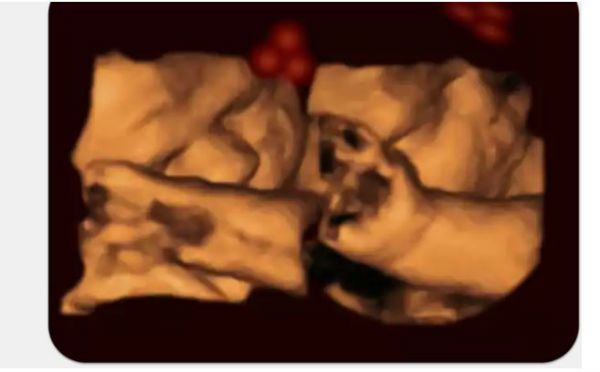

Απίθανες κινούμενες εικόνες εμβρύων πριν από τη γέννα αποδεικνύουν οτι μπορούν να στρέψουν το κεφάλι τους για να κοιτάξουν σχήματα που μοιάζουν με ανθρώπινα πρόσωπα. Όταν όμως βλέπουν ένα απλό σχήμα, απλά το αγνοούν, σύμφωνα με το πανεπιστήμιο του Lancaster .

Οι έρευνες έγιναν με τη βοήθεια φωτεινών κουκίδων που έμοιαζαν με μύτη και μάτια ενός ανθρώπινου προσώπου. Έγινε σε 39 εγκύους που ήταν στην 34η εβδομάδα κύησης (8ο μήνα)

Επίσης αποδείχθηκε οτι τα έμβρυα γύριζαν μόνο όταν έβλεπαν τα συγκεκριμένα σχήματα καθώς όταν άναβαν φωτάκια που έφτιαχναν τυχαία σχήματα, τα έμβρυα έμεναν αδιάφορα.